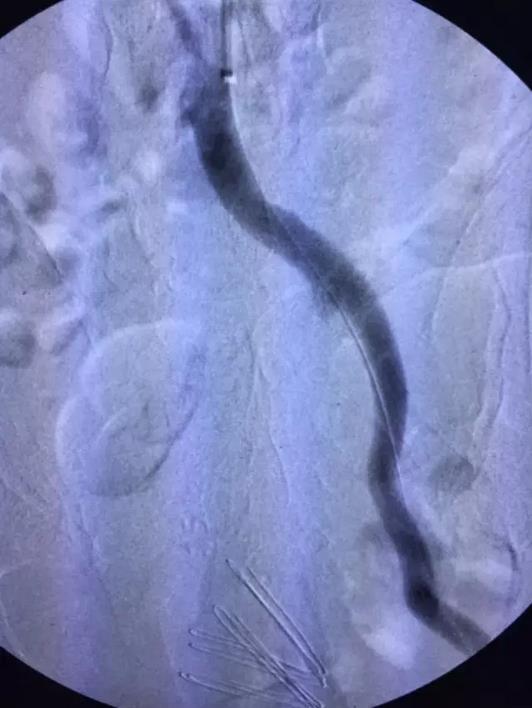

术后因患者长时间留置动脉鞘管,易导致菌血症、鞘管内血栓形成等并发症。施敏护士长带领的护理团队术后严格无菌操作,按时冲洗鞘管,避免了上述并发症的发生。5天后复查造影(图3,4,5,6,7):腹主动脉,左侧髂动脉,股动脉全程通常,膕动脉短段闭塞,但周围侧枝血管丰富,可较好的代偿至膝下。患者左下肢的皮肤温度和颜色明显改善,下肢疼痛,发凉等缺血症状缓解,出院前复查CTA效果良好(图8)。

图3 溶栓后主髂动脉造影

图4 溶栓后股总动脉造影